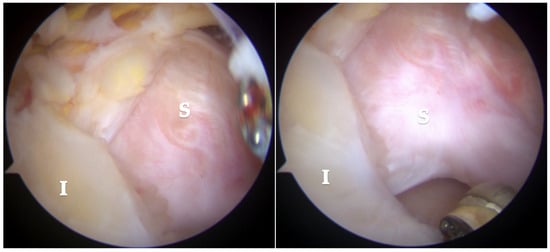

Arthroscopic visualization revealed multiple layers of the rotator cuff. Sheets 2 and 3 of the infraspinatus tendons were identifiable, while only sheet 3 of the supraspinatus tendon was visible, with sheet 2 absent (Figure 3). The mobilization of the rotator cuff confirmed that restoration to the footprint could be achieved without excessive tension (Figure 4).

Figure 3.

Subacromial view demonstrating full-thickness rotator cuff tear involving the supraspinatus (S) and infraspinatus (I) tendons. Only sheet 2 of the supraspinatus tendon is visible, while both sheets 2 and 3 of the infraspinatus tendon are present.

Figure 4.

Reduction maneuvers demonstrated the ability to reposition sheet 3 of the supraspinatus tendon (right image) and sheets 2 and 3 of the infraspinatus tendon (left image) back to their native footprint.

The lesion involved a full-thickness tear affecting both the supraspinatus and infraspinatus tendons, with separation into superficial bursal and deep articular layers. The layers exhibited differential retraction and elasticity; the superficial layers were more retracted compared to the deep layers. The complete reduction of the infraspinatus tendon was achieved, whereas only the deep layer of the supraspinatus tendon could be restored to the footprint due to the excessive retraction and stiffness of the superficial layer. Given the chronicity and severity of the tear, a complete anatomical repair was deemed unattainable. The frayed edges of the tendon were meticulously debrided to prepare for repair. Two suture anchors (Q-FIX 2.8 mm, Smith and Nephew, London, UK) were employed to secure the torn tendon back to its native humeral attachment using a single-row repair technique.